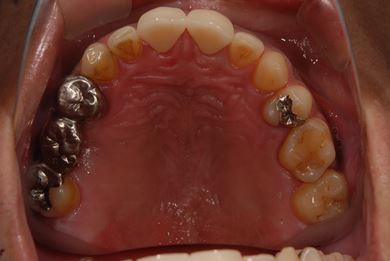

治療前

• 治療前